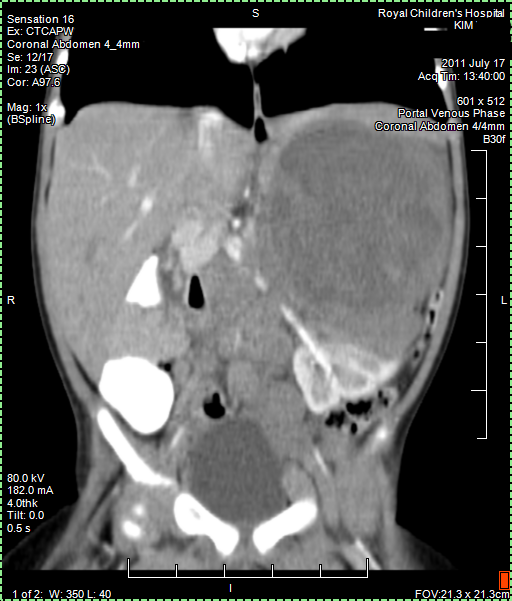

Today we got the Radiology Report back of the 25 August CT (CAT) scan. Papa still has a few remaining questions about it but it confirmed that the tumour shrank as papa thought to see himself from the images. Good news!

Papa collected copy of CT (CAT) scan images from Radiology. Looking at them it seems that the main tumour shrank from around 11 cm to 6 cm and there is less evidence of Nodes. But we have to await Radiology Report to be sure about this positive news. Lets hope Papa is right.

CT (CAT scan) abdomen under anaesthetic, confirms cancer. We await the Radiology Report. There is no way knowing what kind of cancer, but it is suspected maybe Neuroblastoma. We learn that there are different types of Neuroblastoma some of which are low risk and can easily be treated or removed. It is very worrying not knowing more.